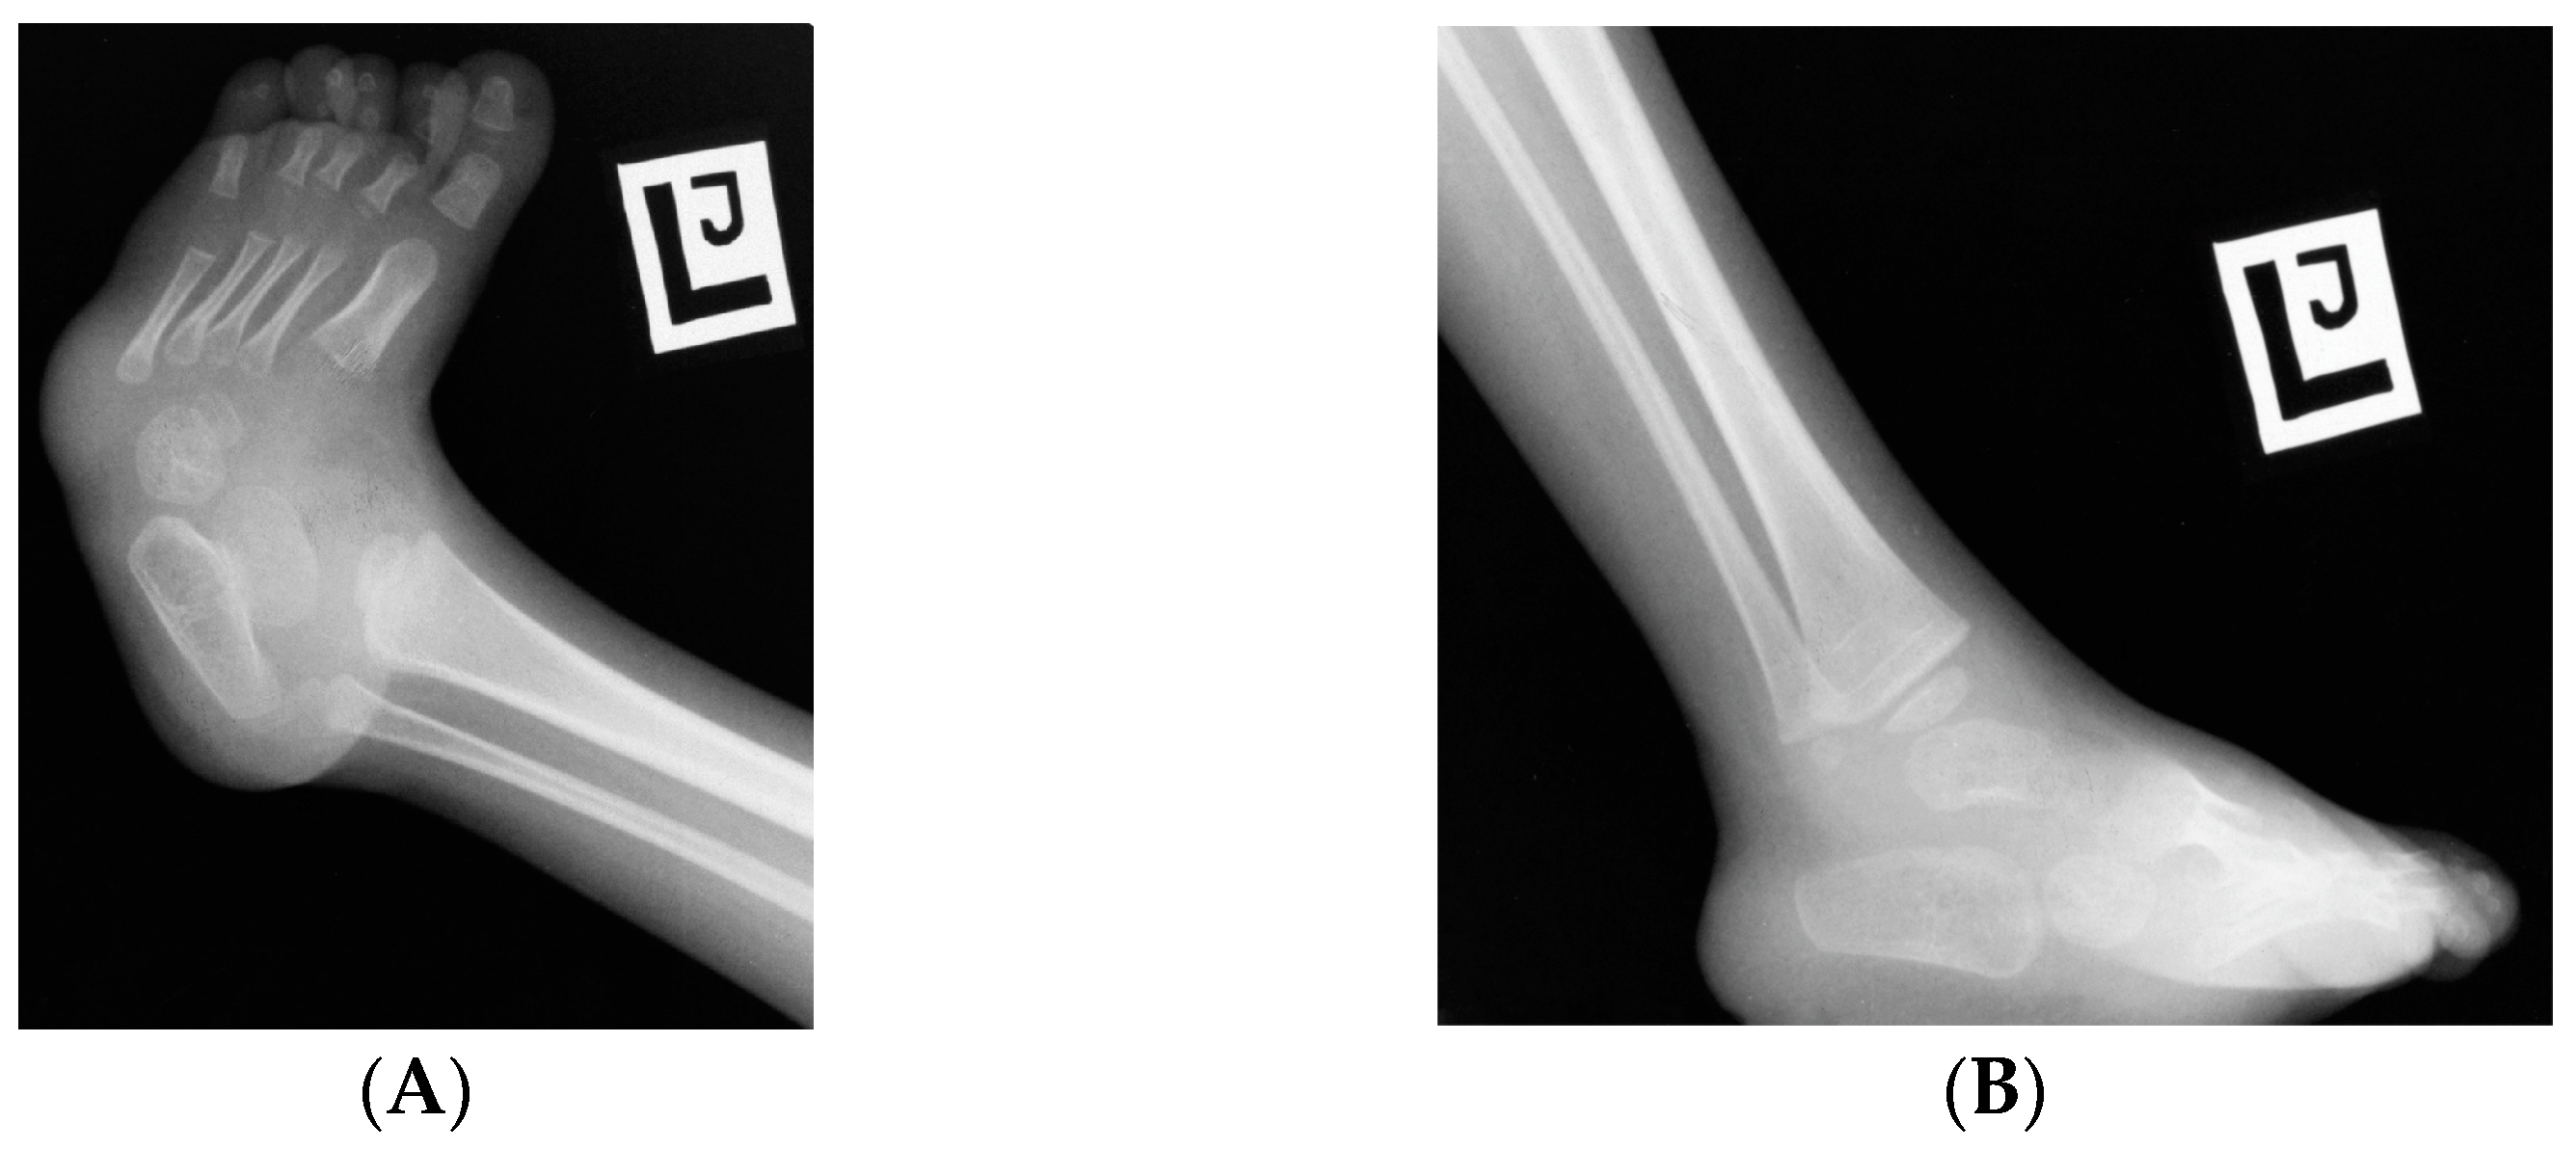

7.2.3. Foot

- Bray, J.J.H.; Crosswell, S.; Brown, R. Congenital talipes equinovarus and congenital vertical talus secondary to sacral agenesis. BMJ Case Rep. 2017, 2017, bcr2017219786. [Google Scholar] [CrossRef]

- Yamamichi, K. Caudal Regression Syndrome with Pressure Ulcers of the Foot: A Case Report. J. Clin. Diagn. Res. 2017, 11, PD19–PD20. [Google Scholar] [CrossRef]